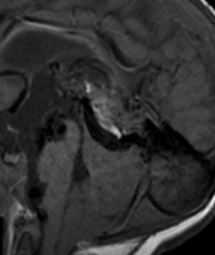

При МРТ головного мозга на аксиальных МРТ любого типа выявляется округлое образование с отсутствием сигнала в области пластины четверохолмия. На сагиттальных МРТ головного мозга отчетливо видно расширение и отсутствин сигнала от расширенной медианной прозэнцефалической вены, а также часто от прямого синуса и синуса намета. При МРА видна расширенная артерия. Тромбированные участки мальформации дают повышенный сигнал на МРТ головного мозга любого типа. На КТ видно скопление контраста в расширенной вене. Ангиография позволяет разделить АВГ на 4 типа в зависимости от питающей артерии.

МРТ головного мозга. Т1-взвешенная сагиттальная МРТ. Аневризма вены Галена.